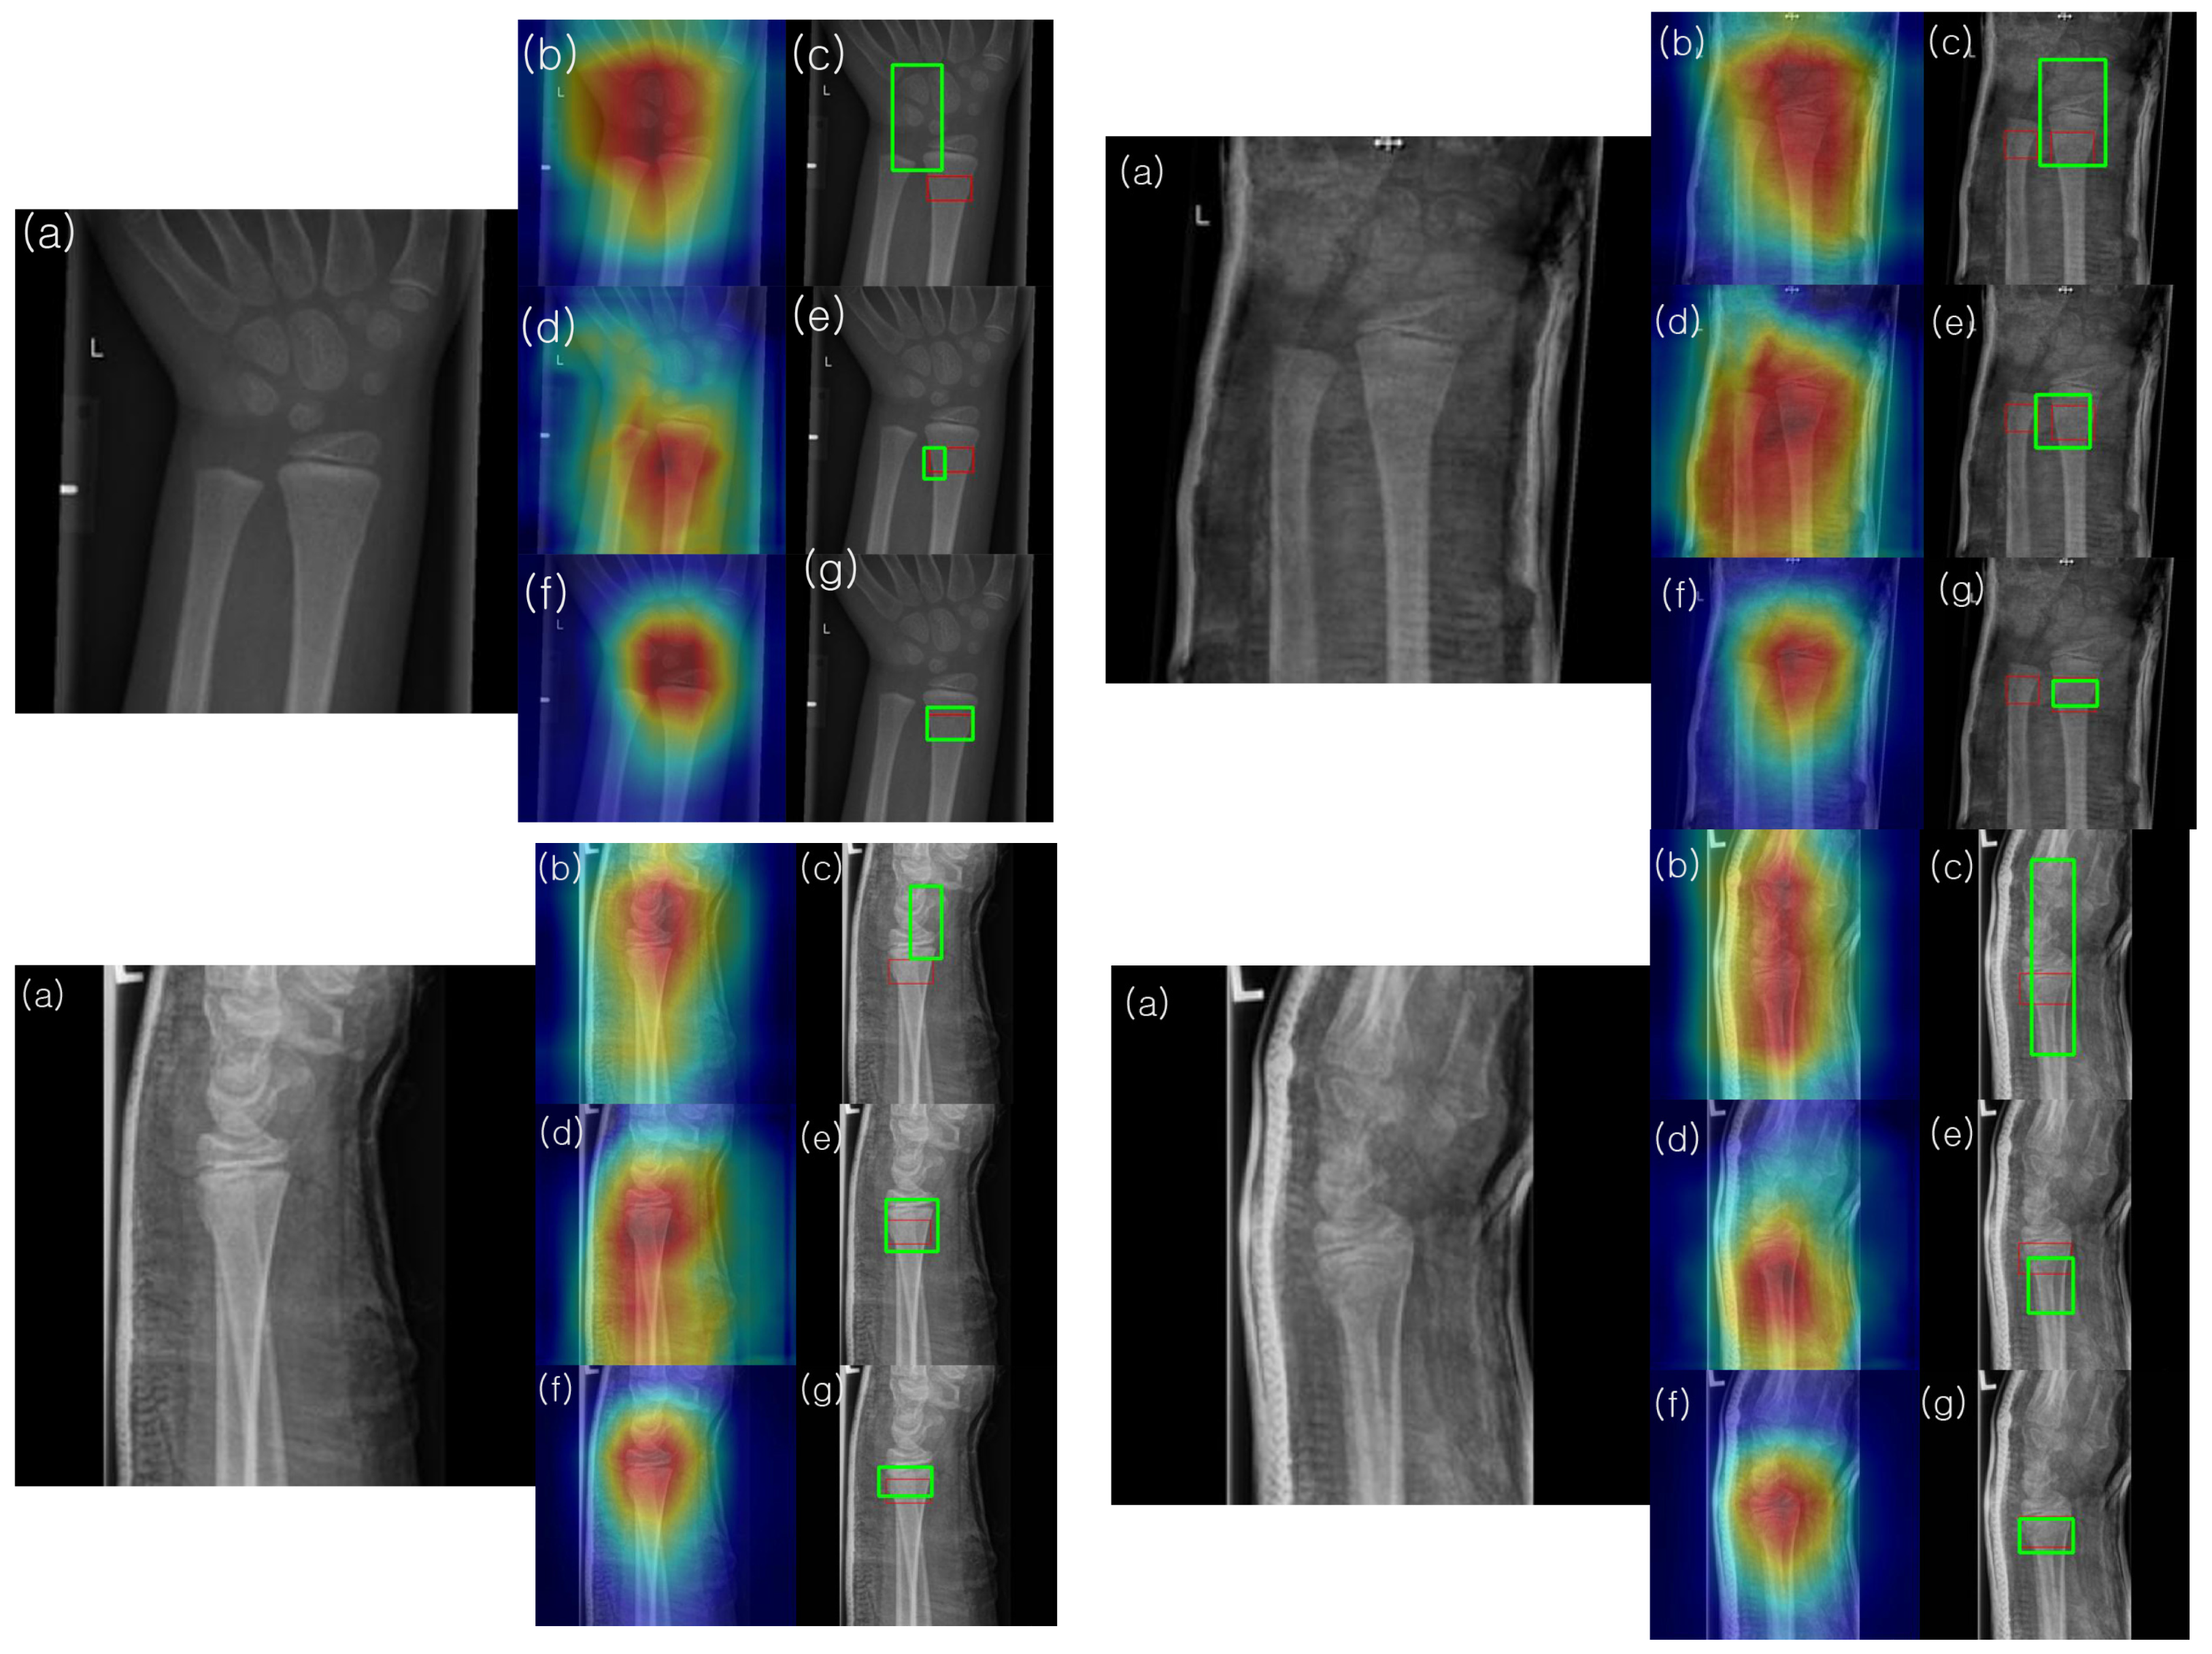

To understand and analyze the learned features of the model, Grad-CAM analysis was conducted on the final convolutional channel using the testing set images. Figure 10 presents the results for four samples from the testing set. Notably, the heatmaps of the model enhanced with HyperColumn-CBAM more consistently highlighted areas with concentrated fractures in the wrist than those obtained with DenseNet169. For the DenseNet169 model, the maximum heatmap area was often located closer to the fracture site than to the pseudo-fracture site, or the heatmap appeared wider. Conversely, for the HyperColumn-CBAM-DenseNet169 model, the maximum heatmap area was located closer to the fracture site and was narrower and thus closer to the area marked by the specialist. It was also observed that the HyperColumn-CBAM-DenseNet169 model, trained by adding coordinate information, was the closest to the area marked by the specialist, which is corroborated by the actual image in terms of the IoU.

Utilizing our Grad-CAM-based color-visualization technique, we identified misalignments in the heatmap produced by the DenseNet169 model. More precisely, the heatmap either mislocalized regions resembling fractures or was overly broad in its depiction. However, when we transitioned to the HyperColumn-CBAM-DenseNet169 model, there was a marked improvement in the Mean of Intersection over Union (MoI), elevating from a mere 0.083 to an impressive 0.213. This can be visualized in Figure 11.

As shown in Figure 10, the model with the coordinates added further aligned with the fracture as marked by the surgeon. Despite these advantages, the object-detection deep-learning architecture is known to require a considerable volume of labeled bounding box training data. In order to detect the presence or absence of fractures and abnormalities in the upper extremity, a vast amount of labeled bounding box data, including fractures, implants, and tissue abnormalities, is required. However, the time of an imaging specialist is valuable, and labeling these disease areas is a time-intensive task. Yet, our proposed model, even when trained only with fracture/non-fracture labeled data without bounding boxes, aligns closely with the fracture site marked by the expert. This makes it highly suitable for large-scale training, offering the advantage of improving training and diagnostic accuracy as acquiring a large volume of surrogate data is relatively easy.

Figure 10. Illustration of the activated image regions for the models in Table 3: (a) input X-ray image, (b) overlay of the input image with the activated heatmap of the DenseNet169 model, (c) predicted square (green) and ground truth squares (red) obtained by thresholding the activated heatmap of the DenseNet169 model, (d) overlay of the input image with the activated heatmap of the HyperColumn-DenseNet169 model, (e) predicted square (green) and ground truth (red) obtained by thresholding the activated heatmap of the HyperColumn-DenseNet169 model, (f) overlay of the input image with the heatmap of the HyperColumn-DenseNet169 model trained by adding coordinate information, (g) predicted square (green) and ground truth (red) obtained by thresholding the activated heatmap of the HyperColumn-DenseNet169 model trained by adding coordinate information.